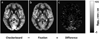

Arterial-spin-labeling (ASL) magnetic resonance imaging (MRI) provides a noninvasive tool to measure cerebral blood flow (CBF) and is increasingly used as a surrogate for baseline neural activity. However, the power of ASL MRI in detecting CBF differences between patient and control subjects is hampered by inter-subject variations in global CBF, which are associated with non-neural factors and may contribute to the noise in the across-group comparison. Here, we investigated the sensitivity of this technique and proposed a normalization strategy to better detect such a difference. A "model" situation was employed in which two visual stimuli (i.e. cross fixation and flashing checkerboard) were presented to two groups of subjects to mimic "control" and "patient" groups (N=7 for each group), respectively. It was found that absolute CBF (aCBF) in the occipital lobe in the checkerboard group was 26.0% greater compared to the fixation group, but the level of significance was modest (P=.03). In contrast, when normalizing the CBF with whole-brain CBF or CBF in a reference region [termed relative CBF (rCBF)], the statistical significance was improved considerably (P<.003). For voxel-based analysis, the rCBF indices correctly detected CBF differences in the occipital lobe in the across-group comparison, while aCBF failed to detect any significant cluster using the same statistical threshold. We also performed Monte Carlo simulation to confirm the experimental findings and found that the power improvement was most pronounced when signal-to-noise-ratio is moderate and the underlying CBF difference was small. The simulation also showed that, with the proposed normalization, a detection power of 80% can be achieved using a sample size of about 20. In summary, rCBF is a more sensitive index to detect small differences in CBF, rather than the much-sought-after aCBF, since it reduces data noise caused by inter-subject variations in global CBF.